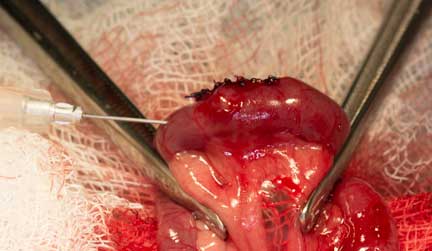

Our surgeon localizes the foreign body and packs the area with gauze before incising into it and removing the FB

Another view of the FB and how stuck it is

Intestine incised and FB removed

A tiny needle with sterile saline is gently injected into the area to make sure there are no leaks before finishing the procedure.